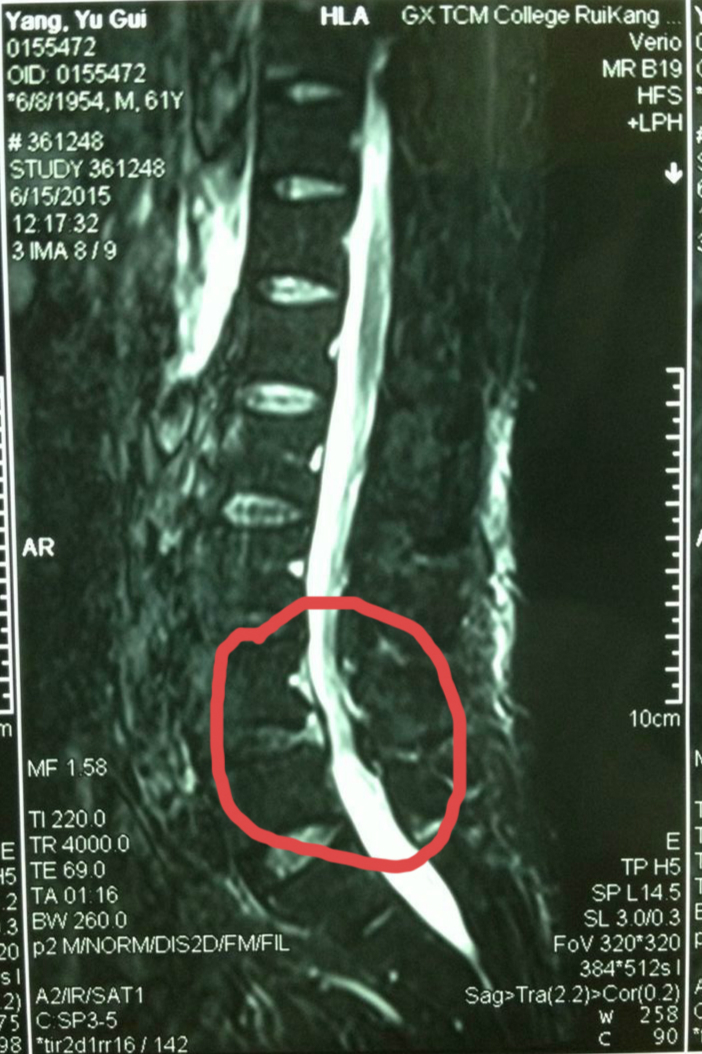

杨老师的主管医生黄保华介绍,杨老师的腰椎间盘突出已导致椎管狭窄,且伴有椎体滑脱。如果实施开放手术,切口会达到10厘米,还需要打钉来固定腰椎,恢复时间至少一个礼拜。现在实施了微创手术,创伤小、恢复快,切口不到一厘米,术后两个小时就能下床走路,大大减轻病人压力。

手术后